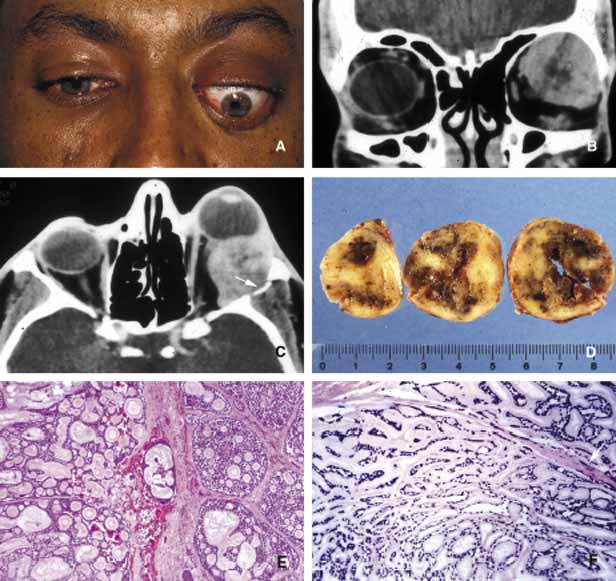

Many metastatic neoplasms originating from other organ systems may find their way to the orbit by hematogenous spread. The most common metastatic malignancies include breast, lung and kidney carcinomas, cutaneous melanoma and rarely sarcomas originating elsewhere in the body.160–162 Tumor-like conditions such as pseudotumors, granulomas, congenital lesions (hamartomas, choriostomas, etc.) that may also invade orbit secondarily are covered elsewhere in this chapter. Both the clinician who evaluates the patient with an orbital space occupying lesion and the pathologist who examines the tissue removed from an orbital mass, must have a working knowledge of the frequency of orbital neoplasms and tumor-like conditions163–166 (Table 4). More commonly encountered acquired orbital neoplasms are detailed. PRIMARY TUMORS Epithelial Neoplasms Primary epithelial neoplasms of the orbit originate from the ductal and acinar epithelium of the lacrimal gland.167,168 The most commonly encountered lacrimal gland tumor is pleomorphic adenoma (benign mixed tumor) (BMT). This neoplasm is known as a “mixed” tumor because it is composed of a mixture of epithelial and stromal elements (Fig. 14). The epithelial elements of the tumor consist of glandular and ductal formations that may develop squamous metaplasia and small keratin filled cysts. The stroma is composed of myxoid tissue that may contain cartilage and bone. In most cases the BMT of the lacrimal gland is multilobulated and surrounded by a fibrous capsule. If additional smaller lobules are present in the vicinity of the main lesion, these satellite nodules are individually encapsulated as well. When malignancy develops within a BMT it is classified according to its predominant histopathologic component as adenocarcinoma within pleomorphic adenoma, adenoid cystic carcinoma, or poorly differentiated carcinoma. Malignant transformation may happen as a rapid growth within an unknown tumor or may take place decades after diagnosis of the BMT.169 Adenoid cystic carcinoma, the most common malignant tumor of the lacrimal gland may also develop de novo. This is a highly malignant neoplasm that can be seen in adolescents and may develop rapid extension into the adjacent structures including the cranium by direct invasion and to the base of the skull by painful perineural invasion.170,171 The histopathologic appearance of adenoid cystic carcinoma may present as several variants including the most common “Swiss cheese” pattern that consists of cribriform clustering of small basophilic tumor cells surounded by thick basement membrane (Fig. 15). Other types including diffuse basaloid, sclerosing, tubular, and comedocarcinoma are known to exist.172 Both benign and malignant tumors of the lacrimal gland present with proptosis and inferior medial displacement of the globe that can readily be demonstrated on CT and MRI studies showing cavitation of the lacrimal fossa in chronic benign lesions and direct invasion of the bony tissues in malignant tumors. Adenocarcinoma developing in BMT (pleomorphic adenocarcinoma, malignant mixed tumor) presents with atypical features within tubular and glandular structures.169 Mucoepidermoid carcinoma of the lacrimal gland consists of diffuse proliferation of atypical squamous cells with abundant vacuolated cytoplasm containing mucin. The clinical course of mucoepidermoid carcinoma is chronic with a relatively favorable prognosis.173,174 Other than true neoplasms, cystic dilatation of the lacrimal gland ductules that is known as dacryops and ectopic lacrimal gland tissue presenting in areas away from the anatomic site of the gland also present as space occupying lesions in the lacrimal fossa.175–177 Mesenchymal Neoplasms The traditional grouping of the primary vascular tumors in the orbit include capillary and cavernous hemangiomas, lymphangioma and arteriovenous malformations. The current thinking is that these lesions represent hamartomas that are made of different tissue components and may be better defined as “vascular hamartomatous lesions.”178 Histopathologic examination of these tumors often reveals mixtures of above listed tissue elements, the symptomatology, clinical course and response to treatment depends on the predominating histopathology. For example, if capillary hemangioma is the dominating element of a vascular tumor it is most often apparent at birth or within the first year, occurs in the anterior orbit and gradually regresses without any treatment. 179 Approximately 70% of capillary hemangiomas regress completely by 7 years of age. Patients with orbital capillary hemangioma may also have similar lesions in other organs. If systemic involvement is extensive, secondary thrombocytopenia known as Kasabach-Merritt syndrome develops. These lesions grossly appear as bright red, strawberry-like masses; histopathologically they are made of sheets of vascular endothelial cells with small lumen formations. Basement membranes surrounding these cells can be clearly identified with a reticulin stain. The predominating cell of the lesion is confirmed to be endothelial cell, by the positive staining for factor VIII, CD31 and CD34. The identification of an intracytoplasmic organelle known as Wiebel-Palade body by transmission electron microscopy also confirms the nature of the tumor cell as vascular endothelium (Fig. 16). For adnexal and orbital capillary hemangioma the treatment options include observation, intralesional and systemic corticosteroids, systemic interferon and in some cases surgical excision and radiation therapy.180–182 Another type of orbital tumor that originates from blood vessels is hemangiopericytoma, which is a pseudoencapsulated spindle cell tumor composed of vascular pericytes183 (Fig. 17). In these tumors the reticulin network surround the individual tumor cells in hemangiopericytoma as opposed to small groups of epithelial cells in capillary hemangioma. In hemangiopericytoma the tumor cells stain positively with factor VIII, CD34, and occasionally vimentin. The histopathologic pattern that may present considerable pleomorphism with increased number of mitotic figures may vary from one zone to the other. The degree of pleomorphism and high number of mitotic figures are not clear cut indications of malignancy; as a matter of fact, the biological behavior of this tumor cannot be determined based on its histopathologic appearance. Metastatases after many years have been described.184 The best treatment for hemangiopericytoma is surgical excision. Cavernous hemangioma is another benign vascular tumor that occurs in adults, usually as a solitary, unilateral lesion, but multiple tumors have been described.185,186 Unlike capillary hemangioma it is not associated with other lesions elsewhere in the body. It is usually located within the muscle cone but may also be seen in extraconal locations and presents with slowly progressive proptosis without too much extraocular motility disturbance (Fig. 18). Gross appearance of cavernous hemangioma is a well encapsulated reddish purple lesion with a sponge-like consistency on its cut surface. Histopathologically, it consists of dilated vascular channels lined by endothelium and smooth muscle and intervening fibrous stroma. The endothelial cells are held together by tight junctions and display basement membrane reduction. Clinical differential diagnosis of cavernous hemangioma on imaging include fibrous histiocytoma, hemangiopericytoma, schwannoma and metastatic tumors.187 Surgical removal of the tumor is the treatment of choice. Another lesion of this category that presents with large cavern formations surrounded by different amounts of fibrous tissue is lymphangioma.188–190 Unlike cavernous hemangioma, however, the space formations in this lesion are not lined by endothelial cells and do not contain vascular smooth muscle; the spaces are lined by flat mesothelial-like cells (Fig. 19). Spontaneous bleeding may take place within these cystic spaces resulting in “chocolate” cysts. In one-third of the cases, lymphoid follicles with germinal centers may be present in the intervening fibrous stroma and some tumors with abundant lymphoid tissue may respond to systemic steroid treatment. Because of the infiltrating nature of this tumor, surgery is not an early option of management; these lesions should be managed conservatively.190 Orbital varix is another orbital vascular lesion that develops as a distention of a venous channel leading to stagnant blood flow resulting in thrombus formation.191 Orbital varices are divided into primary lesions, confined to the orbit and secondary lesions associated with intraorbital and intracranial arteriovenous malformations.54 Vascular hamartomatous lesions may contain arteriovenous malformations with or without abnormal communication between arterial and venous vasculature. These lesions should not be confused with carotid cavernous and dural cavernous fistulas, which affect the orbit secondarily.192 If one clinically suspects an A-V malformation component in an orbital vascular lesion, CT angiogram and arterial and venous angiograms should be used to rule out the connection of the lesion to systemic circulation.193 Color Doppler flow imaging has also been used to examine these tumors. In addition to the above detailed vascular tumors, angiosarcoma, Kaposi sarcoma, intravascular papillary endothelial hyperplasia (IPEH), vascular leiomyoma and angiolymphoid hyperplasia with eosinophilia (Kimura disease), can rarely be encountered in the orbit.194–198 In this chapter, neural neoplasms are covered under two major groups: tumors originating from central nervous system (CNS) tissues, and tumors originating from peripheral nerves. The two most commonly encountered tumors of the optic nerve that involve the orbit are optic nerve glioma and optic nerve meningioma.200 Optic nerve glioma (ONG) is primarily a tumor of childhood.201,202 When it presents in adults a more malignant glioma should be suspected.203 ONG is associated with neurofibromatosis type I (NF-I) with one or both optic nerves involved in approximately 25% of the cases.204 Some authors suggest that patients with NF-I may have a favorable prognosis. In general, the more anterior the glioma, the more favorable the prognosis.205 These tumors produce painless progressive visual loss and proptosis and ophthalmoplegia.206 Optic disc swelling and atrophy is generally present and rarely optociliary shunt vessels may develop.207 Neurofibromatosis (NF) is subdivided into types I and II. It is an autosomal dominant multisystem disease characterized by multiple tumors and developmental abnormalities.208,209 Neurofibromatosis type I presents with numerous ocular adnexal and orbital manifestations including optic nerve and chiasm gliomas and optic nerve sheath meningioma (Fig. 20). Histopathologically ONG is a low-grade pilocytic astrocytoma.210,211 The tumor is composed of proliferating fibrillary astrocytes that may show different degrees of pleomorphism and vascular proliferation (Fig. 21). The axonal component of the nerve is not involved with the neoplastic process during the early stages of the disease. Mitotic figures and necrosis are associated with malignant transformation into higher grades. These tumors show pleomorphic cellular changes, with increased mitotic rate and necrosis. Long standing ONG (”ancient” glioma) may develop degenerative changes including dilated processes of glial cells (Rosenthal fibers) and hyalinization.200 The diagnosis of these tumors has significantly improved with the advances of neural imaging, particularly with MRI and the role of biopsy in the management ONG has become more or less obsolete.212 In unusual cases in which there is rapid tumor enlargement accompanied by visual loss, biopsy may reveal useful information to differentiate between ONG and meningioma and may help in documenting the presence of a malignant glioma. Interpretation of the biopsy sample may be difficult because of the infiltration of the subarachnoid space with pilocytic astrocytes that are similar in appearance to meningeal fibroblasts.213 Another pitfall that should be remembered is that the arachnoidal hyperplasia secondary to ONG may be misinterpreted as a primary meningioma.214 The treatment of ONG includes surgical excision if the extension into the cranium is imminent. Radiation and chemotherapy are generally reserved for patients older than age 5 years with worsening of signs and symptoms.215 Meningioma is a slow-growing tumor originating from the meningoendothelial cells of the arachnoidal layer of the optic nerve or the cranial meninges. These tumors may occur primarily in the optic nerve sheath or extend into the orbit secondarily from the cranial cavity.200 The symptoms of optic nerve meningioma (ONM), which typically affects white, middle-aged females, include slowly progressive, painless loss of vision and proptosis. As the disease progresses, there may be disc edema, orbital ciliary shunts, and optic atrophy.216 Histopathologically meningioma shows varying patterns of meningoendothelial proliferation including sheets of polygonal cells, mixed proliferation of elongated meningoendothelial cells with fibroblasts, and the psammomatous type in which the meningoendothelial cells form eddies to surround calcified psammoma bodies (Fig. 22). Immunohistochemically, they are positive for EMA and vimentin (Fig. 22). Two other types of more aggressive histopathologic patterns are known: the angioblastic and sarcomatous. These lesions have a tendency to recur and extend into adjacent bone and occasionally metastasize. Although a malignant behavior is not predictable in all cases, high mitotic rate implies worse prognosis; cell cycle markers such as MIB-1 may be useful in evaluation of borderline aggressive cases. There is an increased incidence of bilateral and multiple meningiomas in neurofibromatosis I and II.217 ONM is usually diagnosed with ultrasonography, CT and MRI.218 Therefore, biopsy is only needed in atypical cases. Surgical treatment of ONM leads to total loss of vision; therefore, it is saved as a last resort for eyes without vision or for unusually large lesions with potential extension into the cranium. Currently radiation therapy is the treatment of choice from the standpoint of long-term preservation of the vision.219,220 Peripheral nerve tumors of the orbit originate from the ciliary ganglion and from cranial nerves III, IV, V, and VI, which are ensheathed by Schwann cells. Schwannoma (neurolemoma) is a benign tumor that originates from the Schwann cell.221 This adulthood tumor accounts for approximately 1% of all orbital tumors 222 Most cases are solitary and unilateral and have a predilection to the superior orbit originating from the branches of supraorbital or supratrochlear nerves.221–223 Approximately 25% of schwannomas demonstrate enlargement of the superior orbital fissure and invasion of the cavernous sinus on CT and/or MRI.224 Schwannoma generally occurs as an isolated tumor; however, in approximately 10% of cases it is associated with neurofibromatosis.225 Histopathologically this encapsulated tumor is composed of proliferation of Schwann cells that in areas reproduce the pattern of the nerve sheath. The cells that have indistinct cellular borders and oval nuclei form either solid structures (Antoni A pattern) or a loose arrangment in a background of finely granular eosinophilic material (Antoni B pattern) (Fig. 23). Isolated clusters of tumor cells (Verocay bodies) are diagnostic.221,226 Older tumors show degenerative changes with increased areas of myxoid differentiation, collagenation and necrosis. These changes are seen in long-standing tumors that are known as “ancient” schwannomas and on MRI present with a cavitary appearance that can be confused with a cystic orbital tumor.227 Very rarely the schwannoma demonstrates increased cellularity of spindle-shaped cells with pleomorphic nuclei and hyperchromatism.228 The malignant tumor usually presents with a plexiform pattern of irregularly swollen nerve bundles containing spindle-shaped cells. Malignant transformation of schwannoma is very rare but once this occurs the prognosis of “malignant schwannoma” (malignant peripheral nerve sheath tumor) is very poor because of rapid intracranial extension or distant metastasis. Tumor cells of schwannoma stain positive for S-100 protein but the positive immunoreactivity is not specific to this tumor; neurofibroma also demonstrates positive but weaker staining with S-100. On occasion, it may be difficult to distinguish a malignant peripheral nerve sheath tumor from other poorly differentiated sarcomas; in these situations, S-100 and GFAP positivity supports the diagnosis of peripheral nerve sheath origin. Neurofibroma accounts for approximately 2% of all orbital tumors.222 This tumor, which is composed of neoplastic proliferation of Schwann cells, axons, and endoneural fibroblasts, may present as an isolated, diffuse or plexiform lesion. All cases of plexiform tumors and some of the diffuse ones are associated with neurofibromatosis and their other characteristics are also similar.229 The localized type is very rarely associated with neurofibromatosis. The plexiform neurofibroma usually presents at a young age as an eyelid lesion, which has been described with a consistency of “bag of worms.” Histopathologically plexiform neurofibromas consist of intertwined bundles of hypertrophic axons, endoneural fibroblasts, and Schwann cells that are compacted into well-demarcated cylindrical cores (Fig. 20). Diffuse neurofibroma is similar to its plexiform counterpart but the distinct bundle formation is absent. The solitary neurofibroma is also composed of groups of axons, Schwann cells and fibroblasts but it is well circumscribed. All three types stain positive with S-100 protein; however, the reactivity is less intense than schwannoma.230 In patients with neurofibromatosis malignant transformation of neurofibroma into neurofibrosarcoma develops in approximately 20% of cases.231 Choice of treatment for neurofibroma is surgical excision that is easily performed in circumscribed, solitary neurofibromas. This often proves to be very difficult for diffuse and plexiform lesions. Large lesions eventually are treated with exenteration. Other types of peripheral nerve tumors including granular cell tumor, alveolar soft part sarcoma, paraganglioma, melanotic neuroectodermal tumor of infancy, primary neuroblastoma and carcinoid have also been reported to originate in the orbit.232–234 Rhabdomyosarcoma (RMS), which constitutes approximately 1% of all orbital tumors, originates from the primitive mesenchymal cells of the orbital soft tissues, which have the capacity to differentiate toward skeletal muscle.235,236 This sarcoma develops more often in males at approximately the age of 7.237 Based on the predominating histopathological pattern, these tumors are classified into four types: embryonal, alveolar, pleomorphic, and botryoid.238 Pleomorphic and botryoid types are rarely seen in the orbit. Embryonal type is predominantly composed of elongated pleomorphic tumor cells with a centrally located hyperchromatic nucleus surrounded by a considerable amount of eosinophilic cytoplasm (Fig. 24). In embryonal RMS, the tumor cells differentiate along rhabdomyoblastic lines with formation of elongated, spindle cell types (“strap cells”), in which longitudinal and cross striations are sometimes discernible, particularly with phosphotungstic acid-hematoxylin (PTAH) stain. The striations represent the presence of actin and myosin filaments, forming bundles within the cytoplasm of the tumor cell. The banding pattern may be accentuated with the use of immunohistochemical markers (actin, desmin) or with electronmicroscopy.239 Alveolar RMS, however, presents with small nodular tumor masses with a variety of histopathologic patterns; in the prevailing pattern, alveolar tumor cells are loosely adherent to a network of thin interstitial fibrovascular septa; the tumor cells are loosely attached to the connective tissue, and in many areas become freely floating in the alveolar spaces (Fig. 24). Although the prognosis for life in all types of RMS has improved dramatically in recent years because of the multidisciplinary treatment approach, it is still true that embryonal type tumors have a better prognosis than alveolar RMS.240,241 Typical clinical features include the sudden appearance and rapid evolution of unilateral proptosis, associated with early extraocular motility disturbance and extensive eyelid and conjunctival edema. In children who present with this clinical picture, the suspicion of RMS should be high and a biopsy should be performed as quickly as possible. Excisional biopsy is preferred over FNAB, which may lead to erroneous diagnosis because it offers a limited amount of tissue.242 Although chemotherapy and radiation therapy play a significant role in management of these tumors, it is still true that the bulk of the tumor should be removed surgically as much as possible, particularly in anteriorly located lesions.243 Because of different patterns of histopathology several round and spindle cell metastatic and primary neoplasms and pseudosarcomatous lesions including leiomyosarcoma, lymphangioma, malignant peripheral nerve tumors, fibrous histiocytoma, Ewing sarcoma, and metastatic neuroblastoma should be considered in the histopathologic differential diagnosis of RMS.237,244 Immunohistochemical studies (Table 3) and electromicroscopy may be of help in diagnosis of poorly differentiated cases. Because of the morphological overlaps, it is important to wait for the results of permanent histopathologic sections before a management plan is initiated, because benign and inflammatory conditions and pseudotumors may simulate RMS, particularly on frozen-section examination.245,246 Other myogenic tumors of the orbit include smooth muscle tumors, leiomyoma and leiomyosarcoma, which occur very rarely.247–249 Fibrohistiocytic Lesions Some of the spindle cell tumors and tumor-like lesions of the orbit originate from fibroblasts and histiocytic cells. These include fibroma, fibromatosis, fibrosarcoma, and fibrous histiocytoma (FH).250,251 Fibrous histicytoma is the most commonly occurring orbital lesion of this group and according to some it is the most common mesenchymal tumor developing in the adult orbit.252 FH is usually a well-circumscribed lesion, which presents a firm, solid yellowish grey appearance on its cut surface. Histopathologically, it is composed of two primary elements: spindle-shaped fibroblasts and rounded histiocytic cells, which are arranged in an interwoven pattern or in a storiform pattern, radiating from central focal points of condensed collagen (Fig. 25). These tumors can sometimes be confused with hemangioperiocytoma,183,253 as well as other spindle-cell tumors, including solitary fibrous tumor, schwannoma, neurofibroma, meningioma and in cases occurring in children, embryonal rhabdomyosarcoma.254 Although most of these tumors are benign, locally aggressive and malignant lesions are described.255,256 The treatment of FH is surgical excision. Fibrohistiocytic tumors and tumor-like conditions include reactive lesions and neoplasms250,257 (Table 6). Reactive lesions are known as fibromatosis; desmoid and juvenile fibromatosis and nodular faciitis.258,259 Although these lesions are histopathologically benign, they are often locally aggressive and have a high rate of reccurrence, particularly in a restricted anatomic site, such as the orbit. The neoplastic fibrohistiocyic lesions can be broadly categorized into two categories as fibroblastic and fibrohistiocytic tumors. The neoplasms originating exclusively from fibroblasts, namely fibroma and fibrosarcoma, are primarily encountered as a second malignant neoplasm in hereditary retinoblastoma survivors and after radiation treatment.260,261